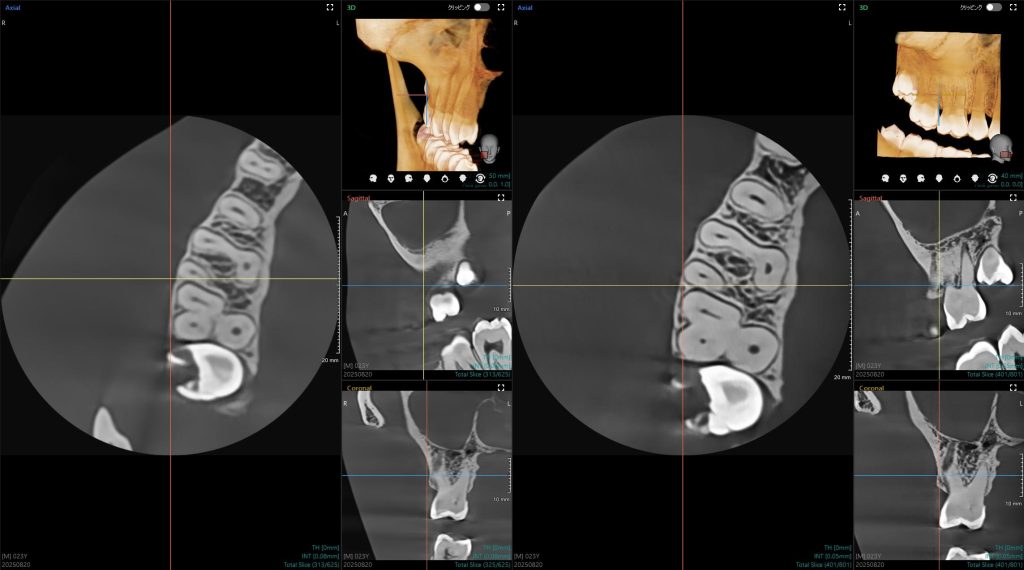

「特に自信を持っているのが、根管治療に特化した『エンドモード』です。ここでは、50ミクロン以下という世界最小クラス※のボクセルサイズを実現しました。※自社調べ/2025年時点

これは他社のハイエンド基準である70ミクロンを凌駕し、まさに髪の毛よりも細い世界を鮮明に描き出します」

※左:従来製品/右:GreenX21

この圧倒的な解像度は、微細な病変や破折線の確認を支え、診断に「確信」をもたらす。実際にCTを使用する先生からは、「あまりにクリアで、これまで診断のために目を凝らし続けていた疲れが癒やされるようだ」という声が寄せられているという。